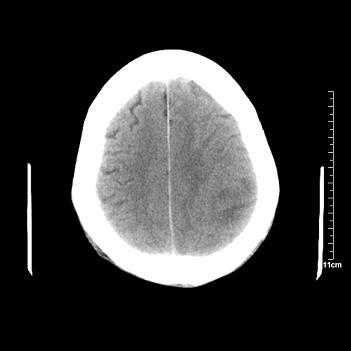

男性患者,72岁,近两天头晕来我院就诊。 因患者血压太高而未做增强,建议病人去市医院做mri检查。等得到mri随访结果再公布给大家。 测及左颞顶枕叶病灶ct值分别为5hu 30hu 729hu。

考虑左侧颞顶枕叶少突胶质细胞瘤。 今天随访患者手术病理结果 病理回报为胶质瘤2级 钙化

左侧颞顶枕叶大片状低密度影,呈均一水样密度,边界清楚,病灶边缘不规则片状钙化,左侧脑室后角扩大,中线结构未见移位,综合来看不像肿瘤,软化灶,钙化不好解释

左侧颞顶枕叶巨大囊性病灶,灶内见小片实性区且灶内及灶周围大量团块状钙化影,灶周水肿少.左侧室枕角内见环形钙化,可见较清晰前壁,钙化与室壁似有间隙.

囊变明显,钙化明显,部分实性组织,轻度占位,左侧脑室受压---考虑 少突胶质细胞瘤,畸胎瘤,寄生虫病

今天追踪患者家属手术病理结果 病理回报为胶质瘤2级并钙化

病理回报为胶质瘤2级并钙化